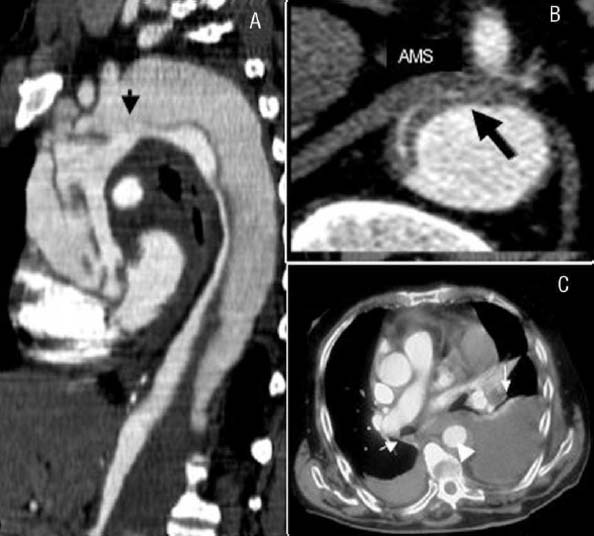

Disección Aórtica (DA)

Una enfermedad catastrófica, no común, cuyo diagnóstico temprano es esencial para evitar mortalidad que supera 50% en los primeros dos días, y es maldiagnosticado con frecuencia en salas de emergencia. Factores de riesgo incluyen: hipertensión arterial, aneurisma Aórtica previa, aterosclerosis, síndrome de Marfan, síndrome de Turner (mujeres); y enfermedades inflamatorias. Dolor desgarrante es el síntoma más común (>90%) (6). Examen físico puede demostrar discrepancias de presión arterial entre brazos, soplo de insuficiencia Aórtica, y presión de pulso ampliada. Pero la ausencia de estos signos no descarta el diagnóstico.

Tomografía axial computarizada (TAC) contrastada de tórax: es el estudio de elección para visualizar el doble lumen o Flap, el colgajo de la disección o la detección de dos luces aórticas.

Figura 2. TAC de diseccion Aórtica